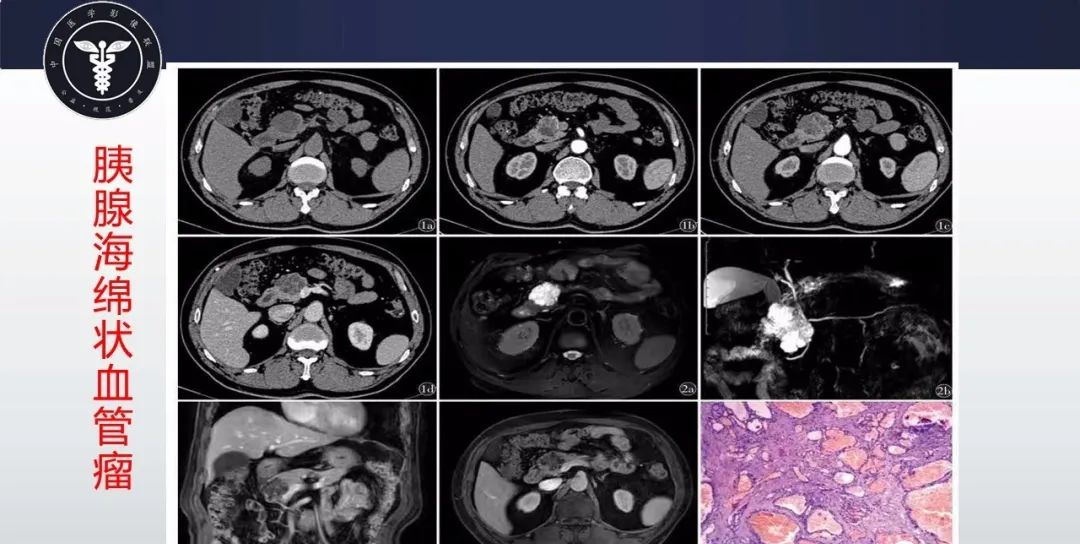

【病例】胰腺血管瘤1例CT及MR影像-5